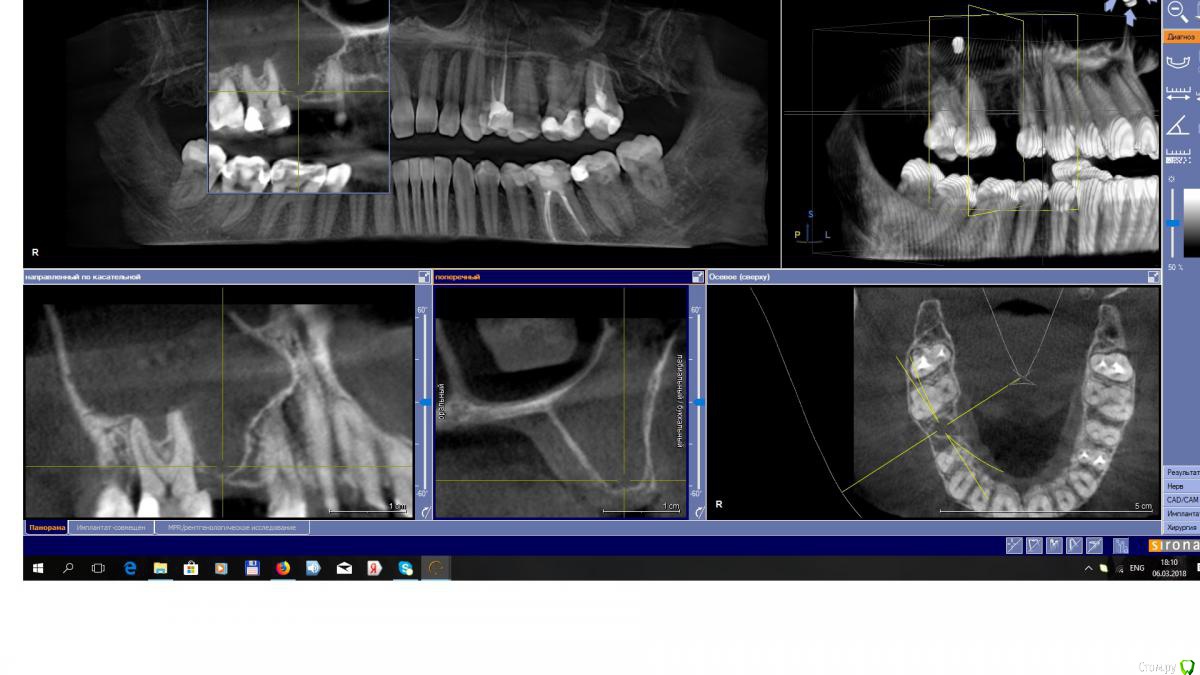

EEcho Опубликовано 13 марта, 2018 Автор Поделиться Опубликовано 13 марта, 2018 Я то же сначала подумал о 16, но ЭОД показала норму, 17 резорциненый уже много лет и без изменений в апикальных тканях.снимки противоположной пазухи прилагаю. Про грибы как то не подумал, с ними ни разу не сталкивался, Спасибо!!! Ссылка на комментарий

red_butler Опубликовано 14 марта, 2018 Поделиться Опубликовано 14 марта, 2018 Вроде последние снимки без пломбировочного Ссылка на комментарий

Irouil Опубликовано 14 марта, 2018 Поделиться Опубликовано 14 марта, 2018 Судя по всему материал удалил, грибковое тело оставил. Доставать ннннада Ссылка на комментарий

EEcho Опубликовано 14 марта, 2018 Автор Поделиться Опубликовано 14 марта, 2018 То то и оно, материал он удалил, но почему то остальное оставил. Хотя со слов пациентки, как ей сказал ЛОР , материал и все остальное он выскоблил. Или, за 2 месяца это все наросло по новой???Раньше отправлял туда же и таких проблем не было. Ссылка на комментарий